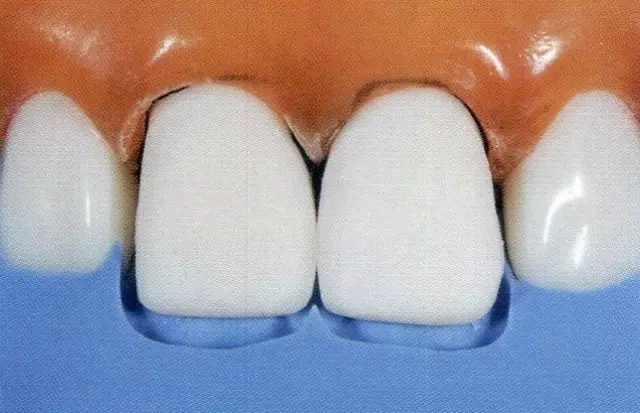

圖7 確認(rèn)唇側(cè)切緣處的切削量。用硅橡膠模型可以確認(rèn)唇側(cè)面的切削量(約0.8mm)。鄰接面預(yù)備深度是隨著鄰接面接觸點(diǎn)有無(wú)、頰舌寬度、鼓形空隙的大小而變化的。

圖8 確認(rèn)唇側(cè)中央處的預(yù)備量。用硅橡膠印模確認(rèn)預(yù)備量。(約0.8mm)